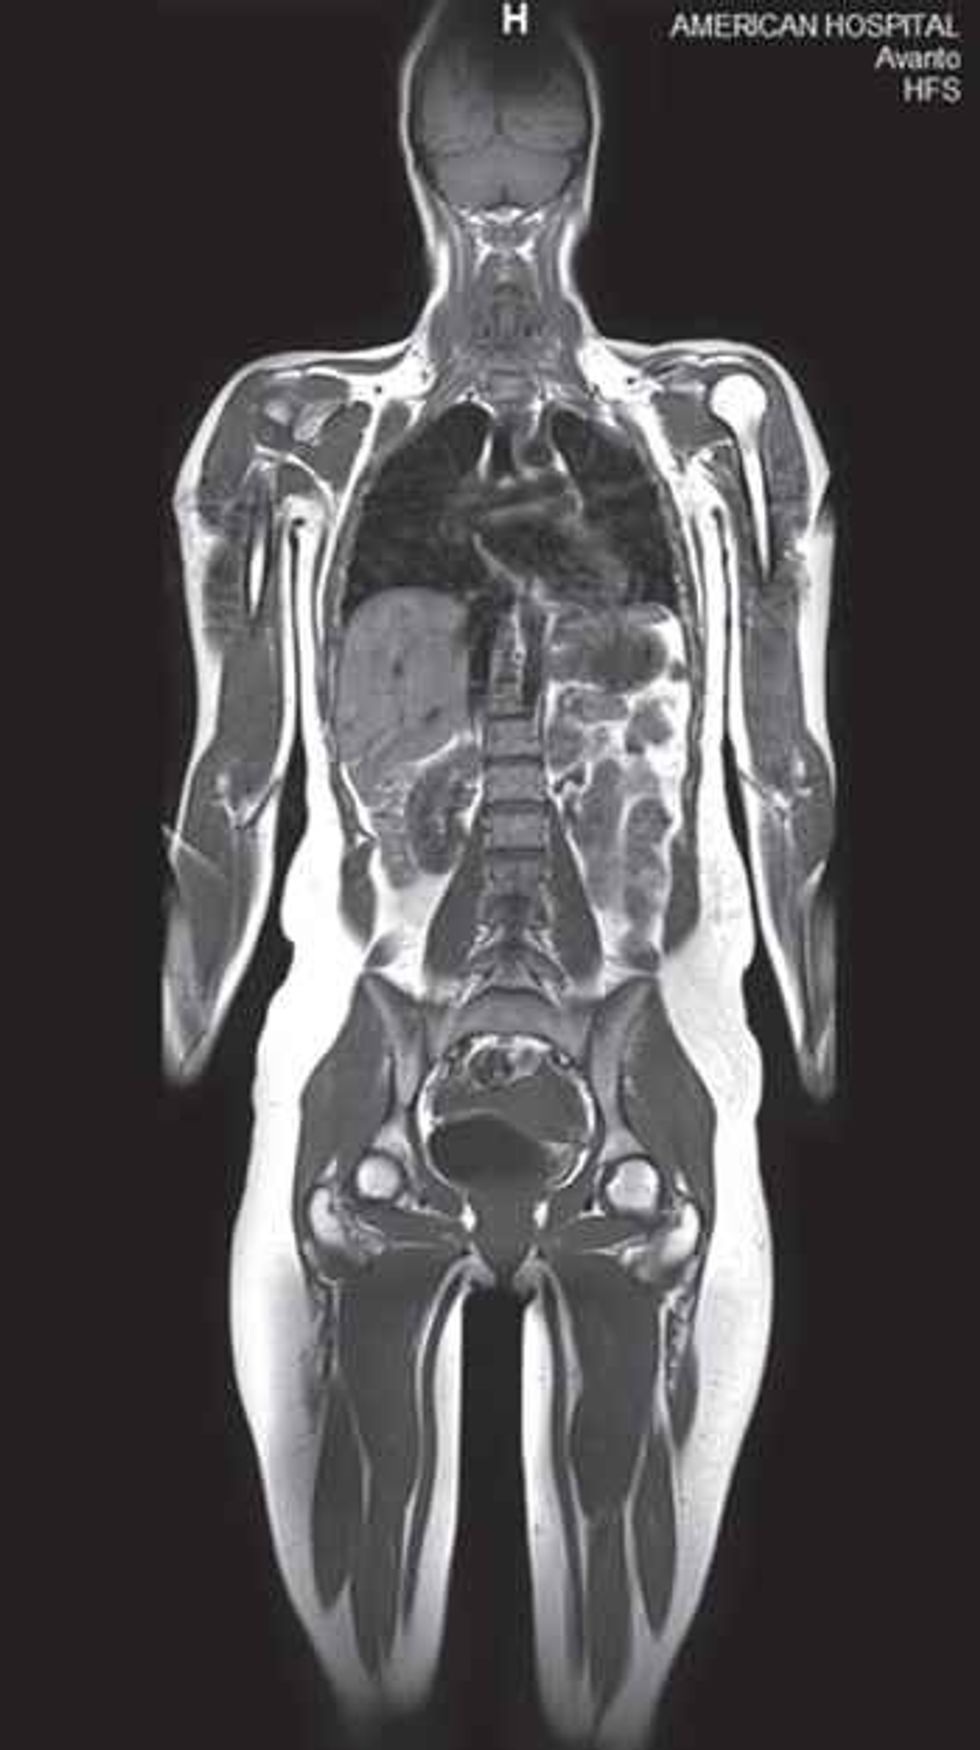

Rezonanca Magnetike e gjithë trupit (whole body MR) është ekzaminim i detajuar i gjithë trupit (nga koka deri te këmbët) që realizohet me anë të sitemit modern TIM të RM dhe përdoret në diagnostikimin dhe percaktimin e shkallës së përhapjes të shume patologjive. /Telegrafi/